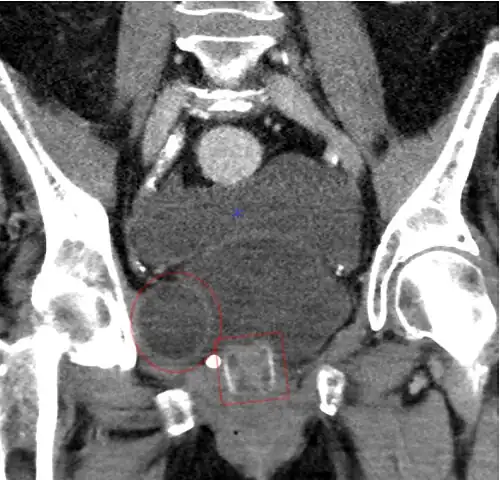

CT scan (coronal reconstruction) showing an AMS 800 in a woman -